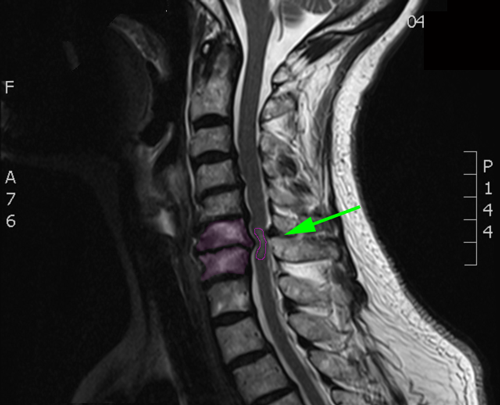

Ασθενής με αυχενική μυελοπάθεια, λευκή περιοχή στο νωτιαίο μυελό (πράσινο βέλος)

Ασθενής με αυχενική μυελοπάθεια, λευκή περιοχή στο νωτιαίο μυελό (πράσινο βέλος)